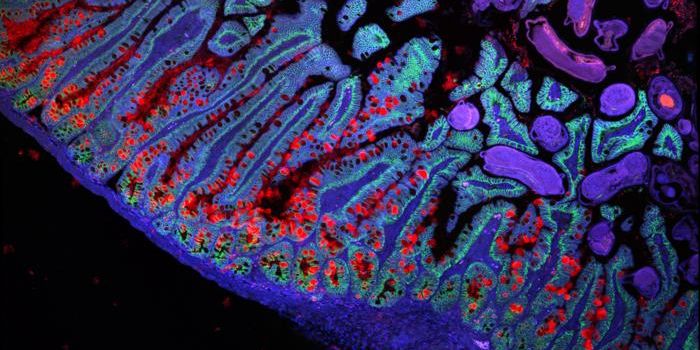

DEC 31, 2024MicrobiologyImage courtesy of Ren Dodge/Carnegie Science shows Lactobacillus (red) in a certain part of the fruit fly gastrointestin ...

DEC 13, 2024Cell & Molecular BiologyThe trillions of microbial cells in our gastrointestinal tract have their own genomes and metabolic products, many of wh ...

DEC 05, 2024Cell & Molecular BiologyResearchers have used a mouse model to show that infections in the intestine can change the composition of bile, a fluid ...

NOV 25, 2024Cell & Molecular BiologyThe significance of the human gut microbiome, a vast community of microbes in the gastrointestinal tract, has been known ...